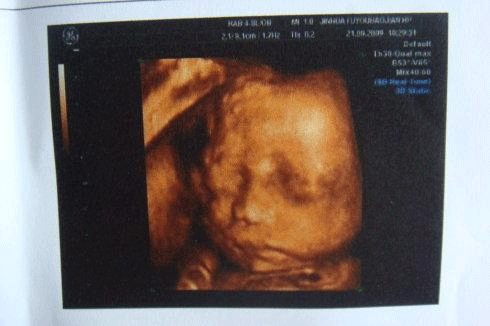

而小排畸和大排畸的区别在检查的方式、时间、目的上,大排畸是在妊娠18—24周做,主要是通过彩超成像的方式来观察胎儿的面部、体表及内脏各器官的发育情况。

而小排畸的检查方式一般会使用高分辨力的彩色多普勒血流显像仪检查,主要是四维彩超一般黑白B超只要求进行上述常规超声检查内容,一般不用黑白B超进行详细系统胎儿畸形超声检查。

一般大排畸都是采用的四维彩超检查,主要观察染色体异常标记,监测胎儿在宫内的发育情况。而小排畸只需做普通B超就可以,因为此时胎儿已经到了孕晚期,通过普通B超就能看到是否存在异常。